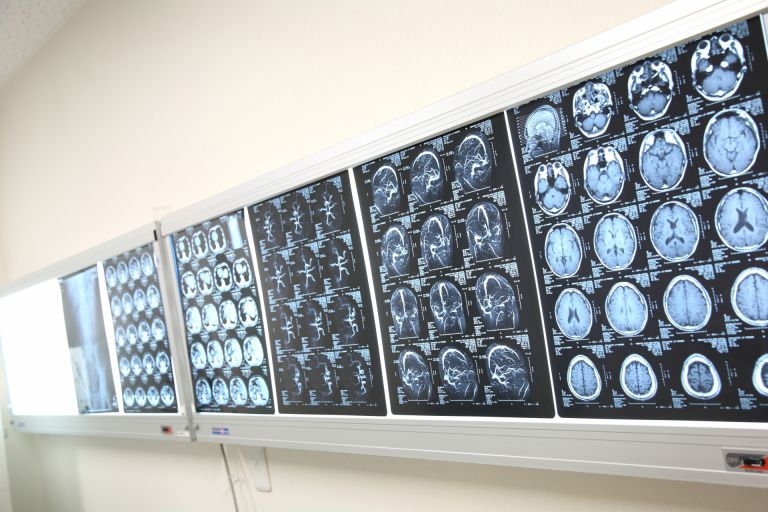

オフィスワーカーが集まるエリアでは、仕事の合間に通院できる環境が重視されている。そのため、診療時間を従来よりも柔軟に設定する医院が多い。朝早い診療開始や昼休み時間帯の診察対応、また夕方遅い時間まで診療を行うところも少なくない。こうした工夫は、忙しいビジネスパーソンが働きながらでも健康維持や早期の体調回復を可能にする生活導線の一部になっている。加えて、一部の病院やクリニックでは、急な発熱や軽度のけがにも迅速に対応できる体制を整えており、小規模ながら院内で血液検査やレントゲン撮影、心電図検査を行う機器を揃えている施設もある。

診療時間もビジネスパーソンの働き方に合わせて柔軟に設定されており、朝早くから夜遅くまで診察を行う医院や、昼休みの時間帯に対応する施設も多く見られます。また、院内で血液検査やレントゲンなどの検査ができるクリニックもあり、短時間で診断や治療が受けられる利便性が評価されています。加えて、外国人出張者への対応や電子カルテ、Web予約システムの導入も進み、スムーズな診療が可能となっています。企業向けの健康診断や人間ドックも広く行われており、各種の健康管理サービスが充実しています。ビル内クリニックは重症対応には限界があるものの、総合病院や救急機関と連携することで、幅広い医療ニーズにも対応しています。